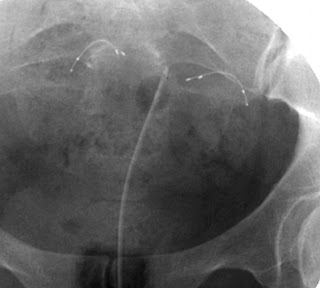

. Irreversible tubal occlusion with a microinsert. (a) Scout radiograph obtained prior to the instillation of contrast material shows a microinsert that has been placed hysteroscopically into the proximal fallopian tube. (b) Radiograph obtained after instillation shows no contrast material filling of the fallopian tube beyond the microinsert, a finding that helps document tubal occlusion.